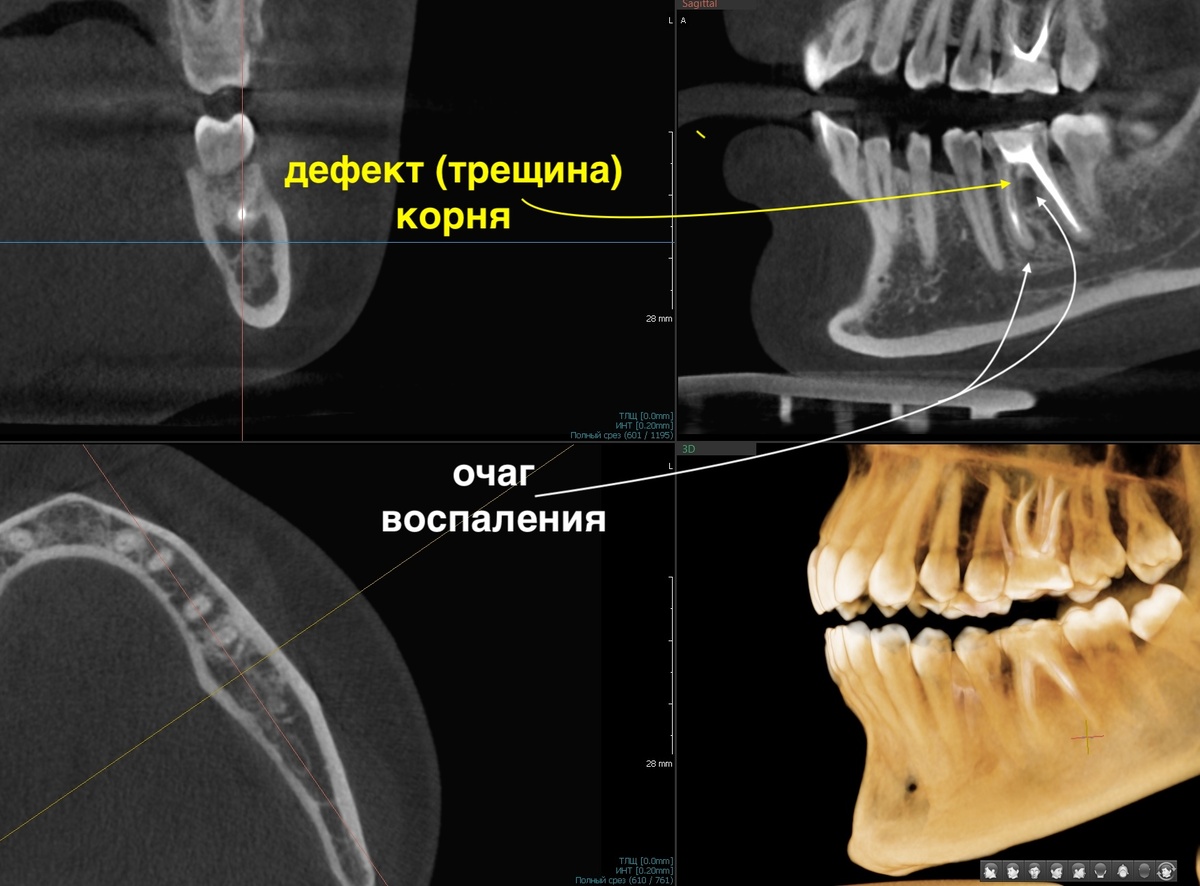

Зуб слева (3.6):

Зуб 3.6, периодонтит

На КТ визуализируются очаги деструкции костной ткани. Один из них нетипичный - в зоне бифуркации, там, где корни расходятся. Причина фатальная, зачастую. Тут наблюдаем дефект корня, видим линию трещины. Треснувший корень - это приговор. Такой зуб не вылечить.